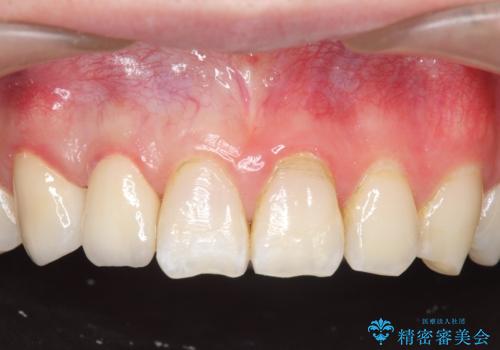

- 右上2、3番目の歯の色・形が気になるといらっしゃった方の症例です。

古い樹脂を除去後、オールセラミッククラウンによる補綴を行いました。

今回用いたオールセラミッククラウンは、ジルコニアフレームという白い素材の上にセラミックを盛っているため審美性が非常に高いのが特徴です。